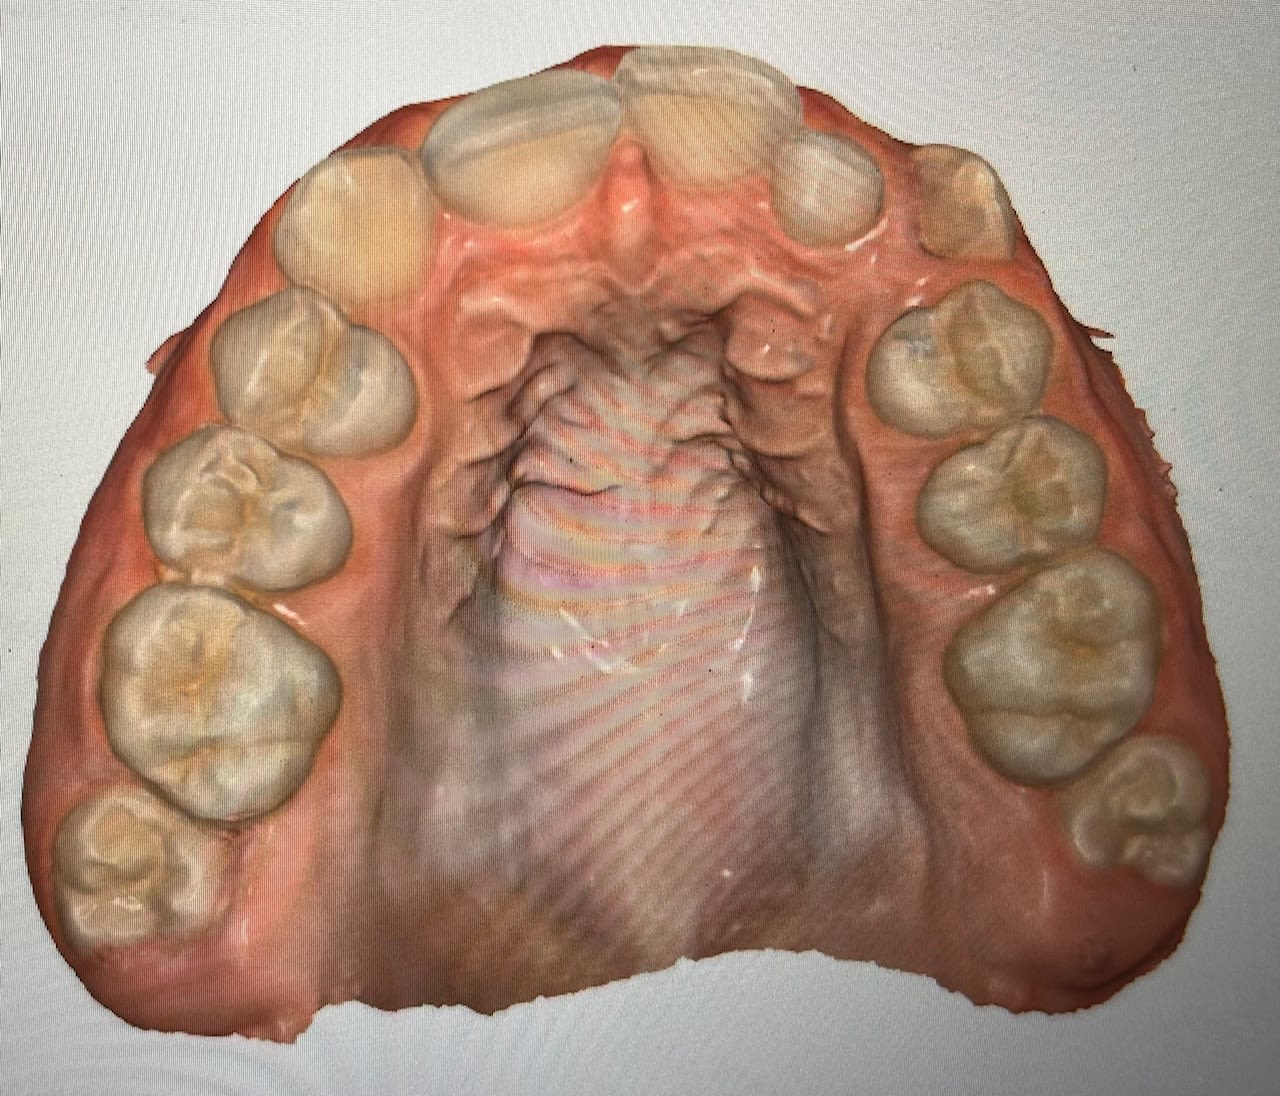

Jeune fille de 11 ans et demi, hypodivergente tendance classe III squelettique (mais classe II dentaire) et biretroalveolie. Agénésie de 12 avec évolution de 13 à sa place et 22 rhyziforme.

Pour ouverture espace et remplacement 12 je pensais à :

- un motion carrière classe II pour commencer à corriger la classe II et ouvrir l’espace de 12. Puis poursuivre avec le multi attache Genius.

- extraction des 4PM1 et alignement. Mais délétère pour le profil … ⚠️

Vous partiriez plutôt à faire un alignement sans extraire 22 et conserver 13 en place de 12?

Procéder à l’alignement et conserver 22 et 13 en place de 12 peut être la meilleure solution selon vous ?

Dans ces cas relativement fréquents d’agénésie d’incisives latérales, on a plutôt tendance aujourd’hui à traiter par fermeture d’espace pour éviter au maximum les prothèses et les implants antérieurs, sources potentielles de problèmes futurs. Vous êtes capable, vous, de garantir un bridge cantilever ou un implant 80 ans (voir l’espérance de vie…) ?

Ici, le plan de traitement de fermeture d’espace me paraît d’autant plus évident qu’on est déjà en classe II molaires :

Avulsion 22 et mésalisations supérieures (on parfait la classe II molaires des 2 côtés).

Moyens : TIM (on peut allègrement prendre appui sur l’arcade inférieure puisqu’on doit même faire de la place pour les incisives). Si c’est insuffisant, VIS au niveau antérieur, de chaque côté de l'orifice piriforme.

On finit en classe II canines thérapeutiques avec des coronoplasties de 13 et de 23.